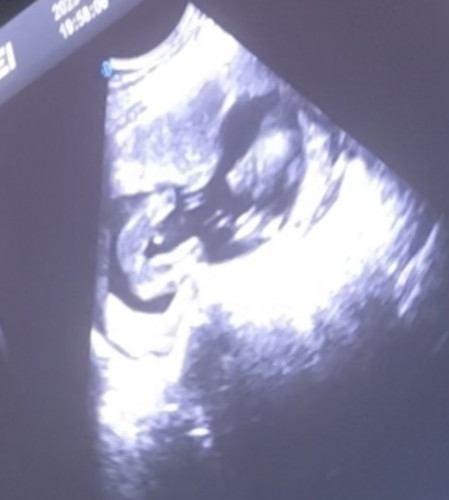

ในรูปลักษณะแบบนี้ จะเป็นผู้หญิงหรือผู้ชายคะ 18wk ขอดูรูปซาวด์ของแม่ๆหน่อยค่ะ